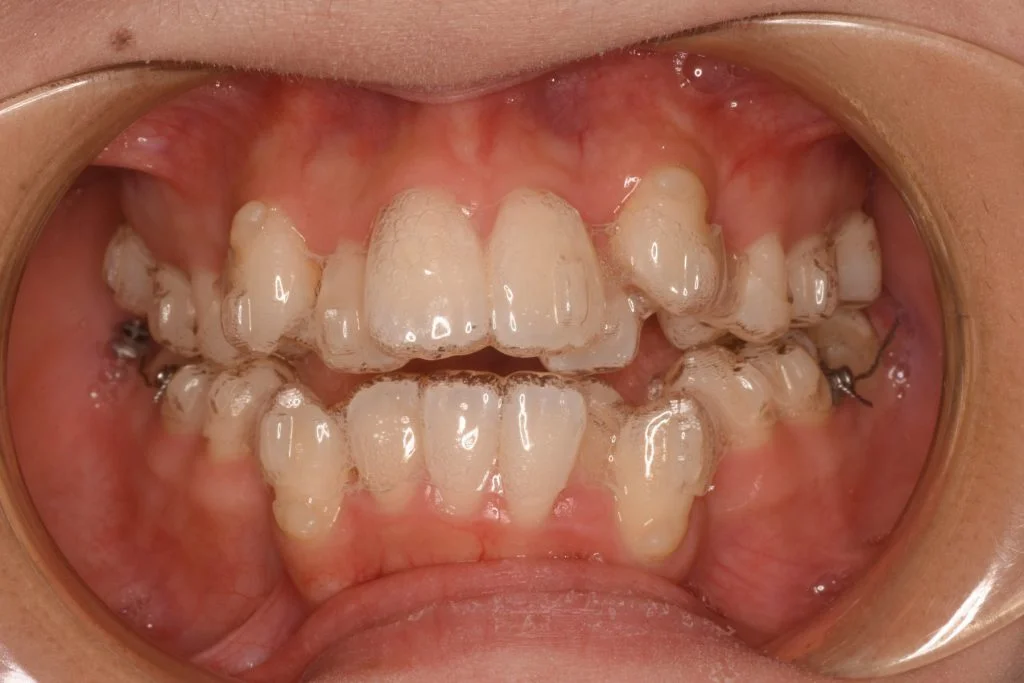

• 症例1-2治療前

マウスピース装着時の写真

• 症例1-2治療後

1年経過時 大体1年で八重歯やガタガタは解消されます